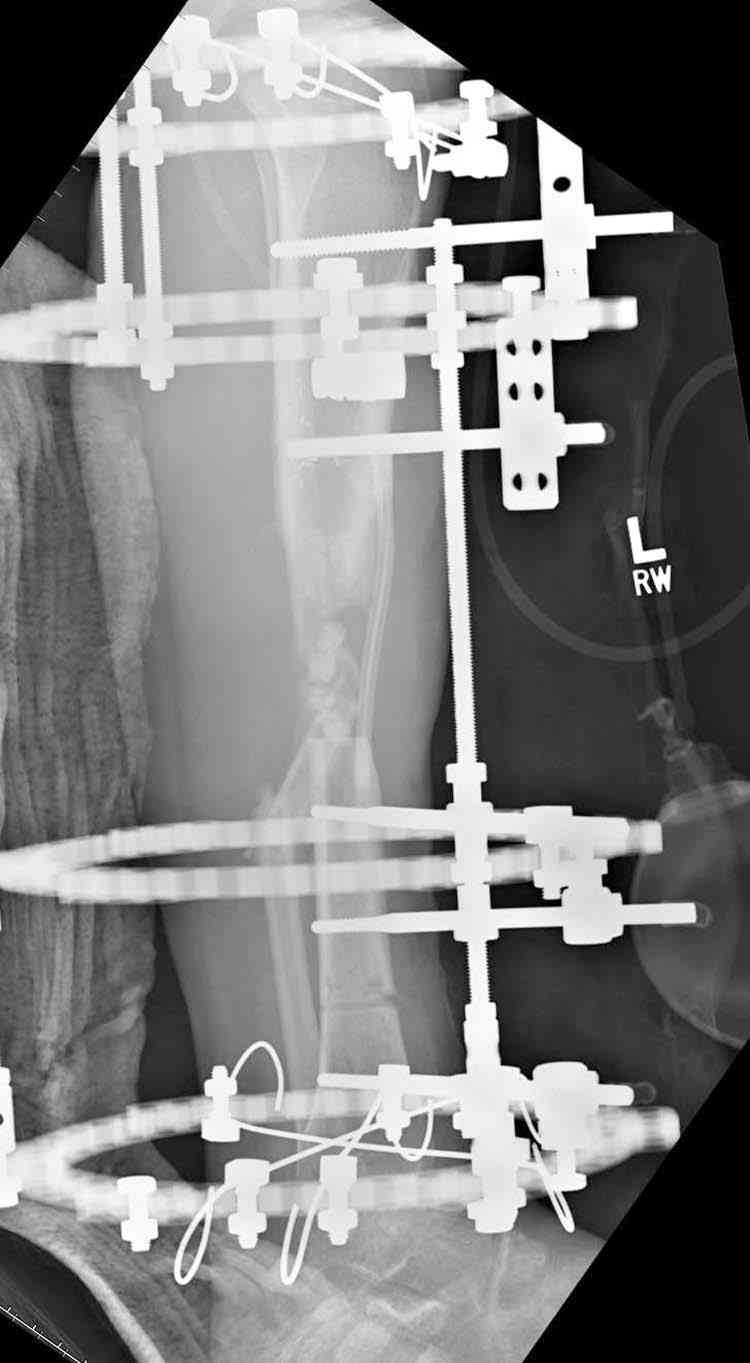

Согласен с тобой, короткий дистальный фрагмент, нет места ни для штифта, ни Т-образной пластины, да и шурупы мешают.

сделать поперечную остеотомию диафиза, полость заполнить antibiotic beads и начать удлинение.

Из аппаратов предпочтительно циркулярный, на дистальном фрагменте можно увеличить количество спиц.

Здесь случай, хотя не тот уровень, но принцип "удлинения после заполнения дефекта Antibiotic Beads" сохранен, можно немного увеличить количество бус.